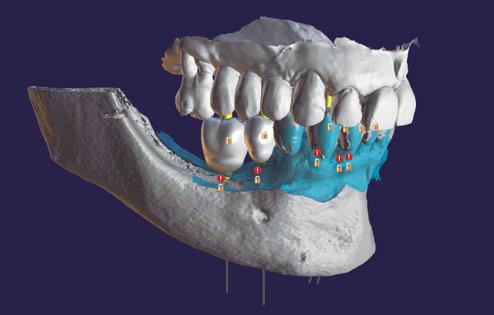

–Planificación de cirugía guiada de implantes con sistema de guía quirúrgica sin anillas metálicas: a propósito de un caso clínico, por el Dr. Antonio García Sanz y cols. [64]

Planificación digital y cirugía guiada para dummies. Cómo confeccionar una guía quirúrgica de un modo predecible, por el Dr. Giuliano Fragola.